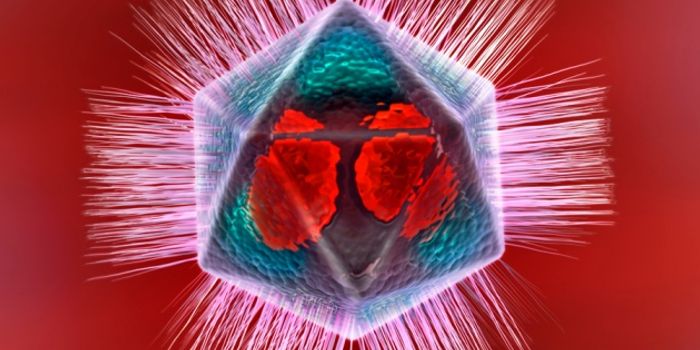

MAR 01, 2016ImmunologyThe first gigantic mimiviruses were discovered in 2007 by a research group of France. They named the virus they found &l ...